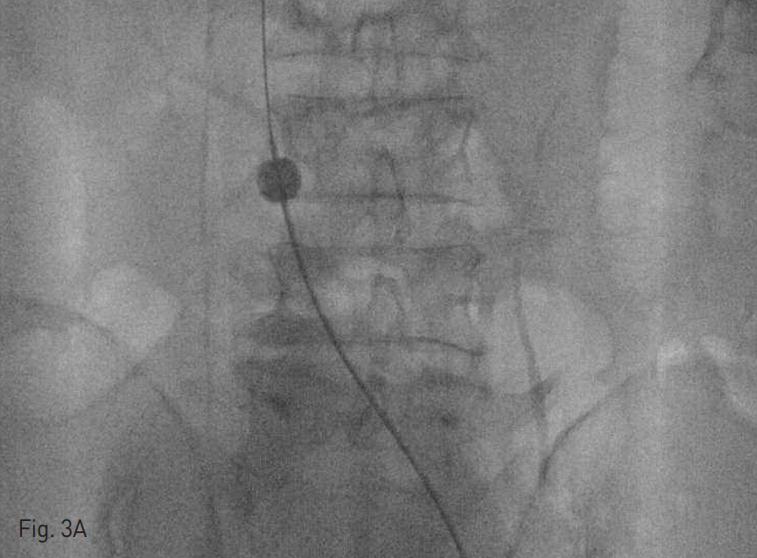

복부 전산화 단층촬영에서 간내부와 간하부의 하대정맥을 따라서 광범위한 혈전이 관찰되었고 양측 신 정맥과 장골정맥까지 혈전증이 동반되어 있었음 (Fig. 1).

Fig. 1

Diffuse thromobosis are in intrahepatic IVC (A), left renal vein (B), and both iliac veins (C)